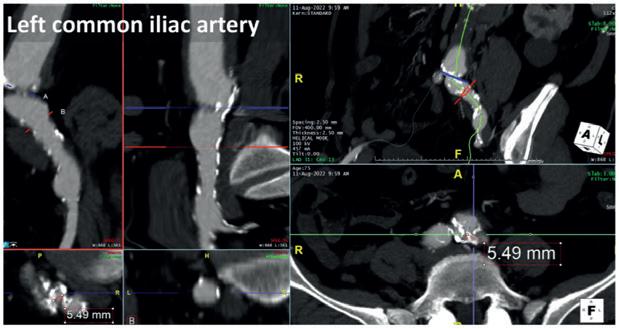

Herein we report the case of a 75-year-old male patient treated in 2009 for infrarenal ruptured abdominal aortic aneurysm (AAA) who developed a proximal pararenal anastomotic pseudoaneurysm of 55mm in maximum axial diameter (Figure 1)

As the patient was a poor candidate for open repair, we opted for an E-nside fourinner-branched, pre-cannulated endograft (Artivion). The major concern about the proposed approach was that the vascular

accesses as a tight circumferential calcified stenosis affected the bilateral origins of the common iliac arteries (Figure 2). Because of this obstructive disease, the femoral pulses were weak, with biphasic wave form bilaterally detected by duplex ultrasound during preoperative evaluation.

Furthermore, two large lumbar arteries arose from the aortic bifurcation and therefore the plan consisted of a distal landing inside the previous aorto-aortic surgical graft, avoiding sacrificing these vessels in order to reduce the risk for spinal cord ischaemia (Figure 3). Moreover, the aortic arch and descending thoracic aorta, as shown in Figure 4, presented irregular floating thrombotic apposition, imposing the need to avoid an upper extremity access and thus the need for both iliac arteries to accomplish endovascular reconstruction.

After preparing both femoral accesses for percutaneous manipulation with two Proglide vascular closure devices (Abbott) using the pre-close technique, an M5+ 8x60mm catheter was advanced over a 0.014” just at the level

of the right common iliac artery stenosis, delivering five cycles of energy (150 pulses overall; Figure 5). The new M5+ catheter halves the time needed for treatment, doubling the pulse delivery to two pulses per second. The exact same procedure was repeated using the remaining five cycles of energy with the same catheter on the contralateral side, to further modify the vessel compliance at the origin of the left common iliac artery.

A control computed tomography angiography (CTA) was performed on postoperative day two as per institutional protocol, confirming the intraoperative findings and revealing a significant luminal gain at the treated segments that was especially evident on the right (Figure 6).